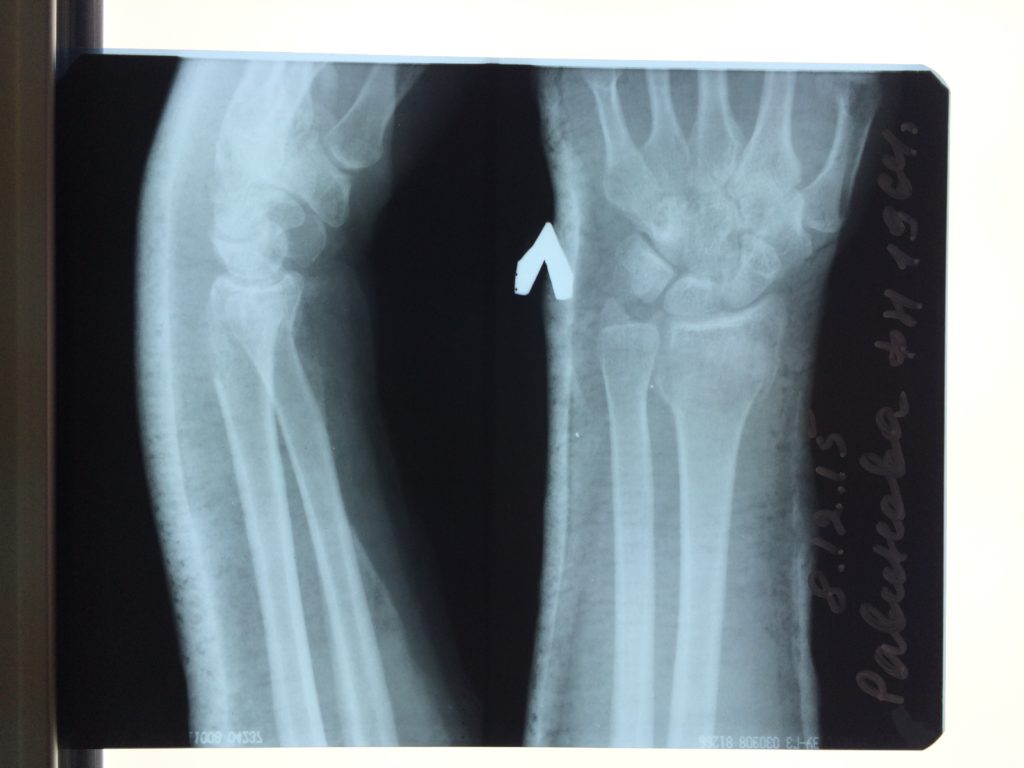

Операция - открытая репозиция, остеосинтез лучевой кости пластиной с костной ксенопластикой материалом "Остеоматрикс". На контрольных снимках в три месяца имеется консолидация перелома, миграции фиксатора нет, имеется остеоинтеграция ксенопластического материала.

Отдаленные результаты через 6 (шесть) месяцев